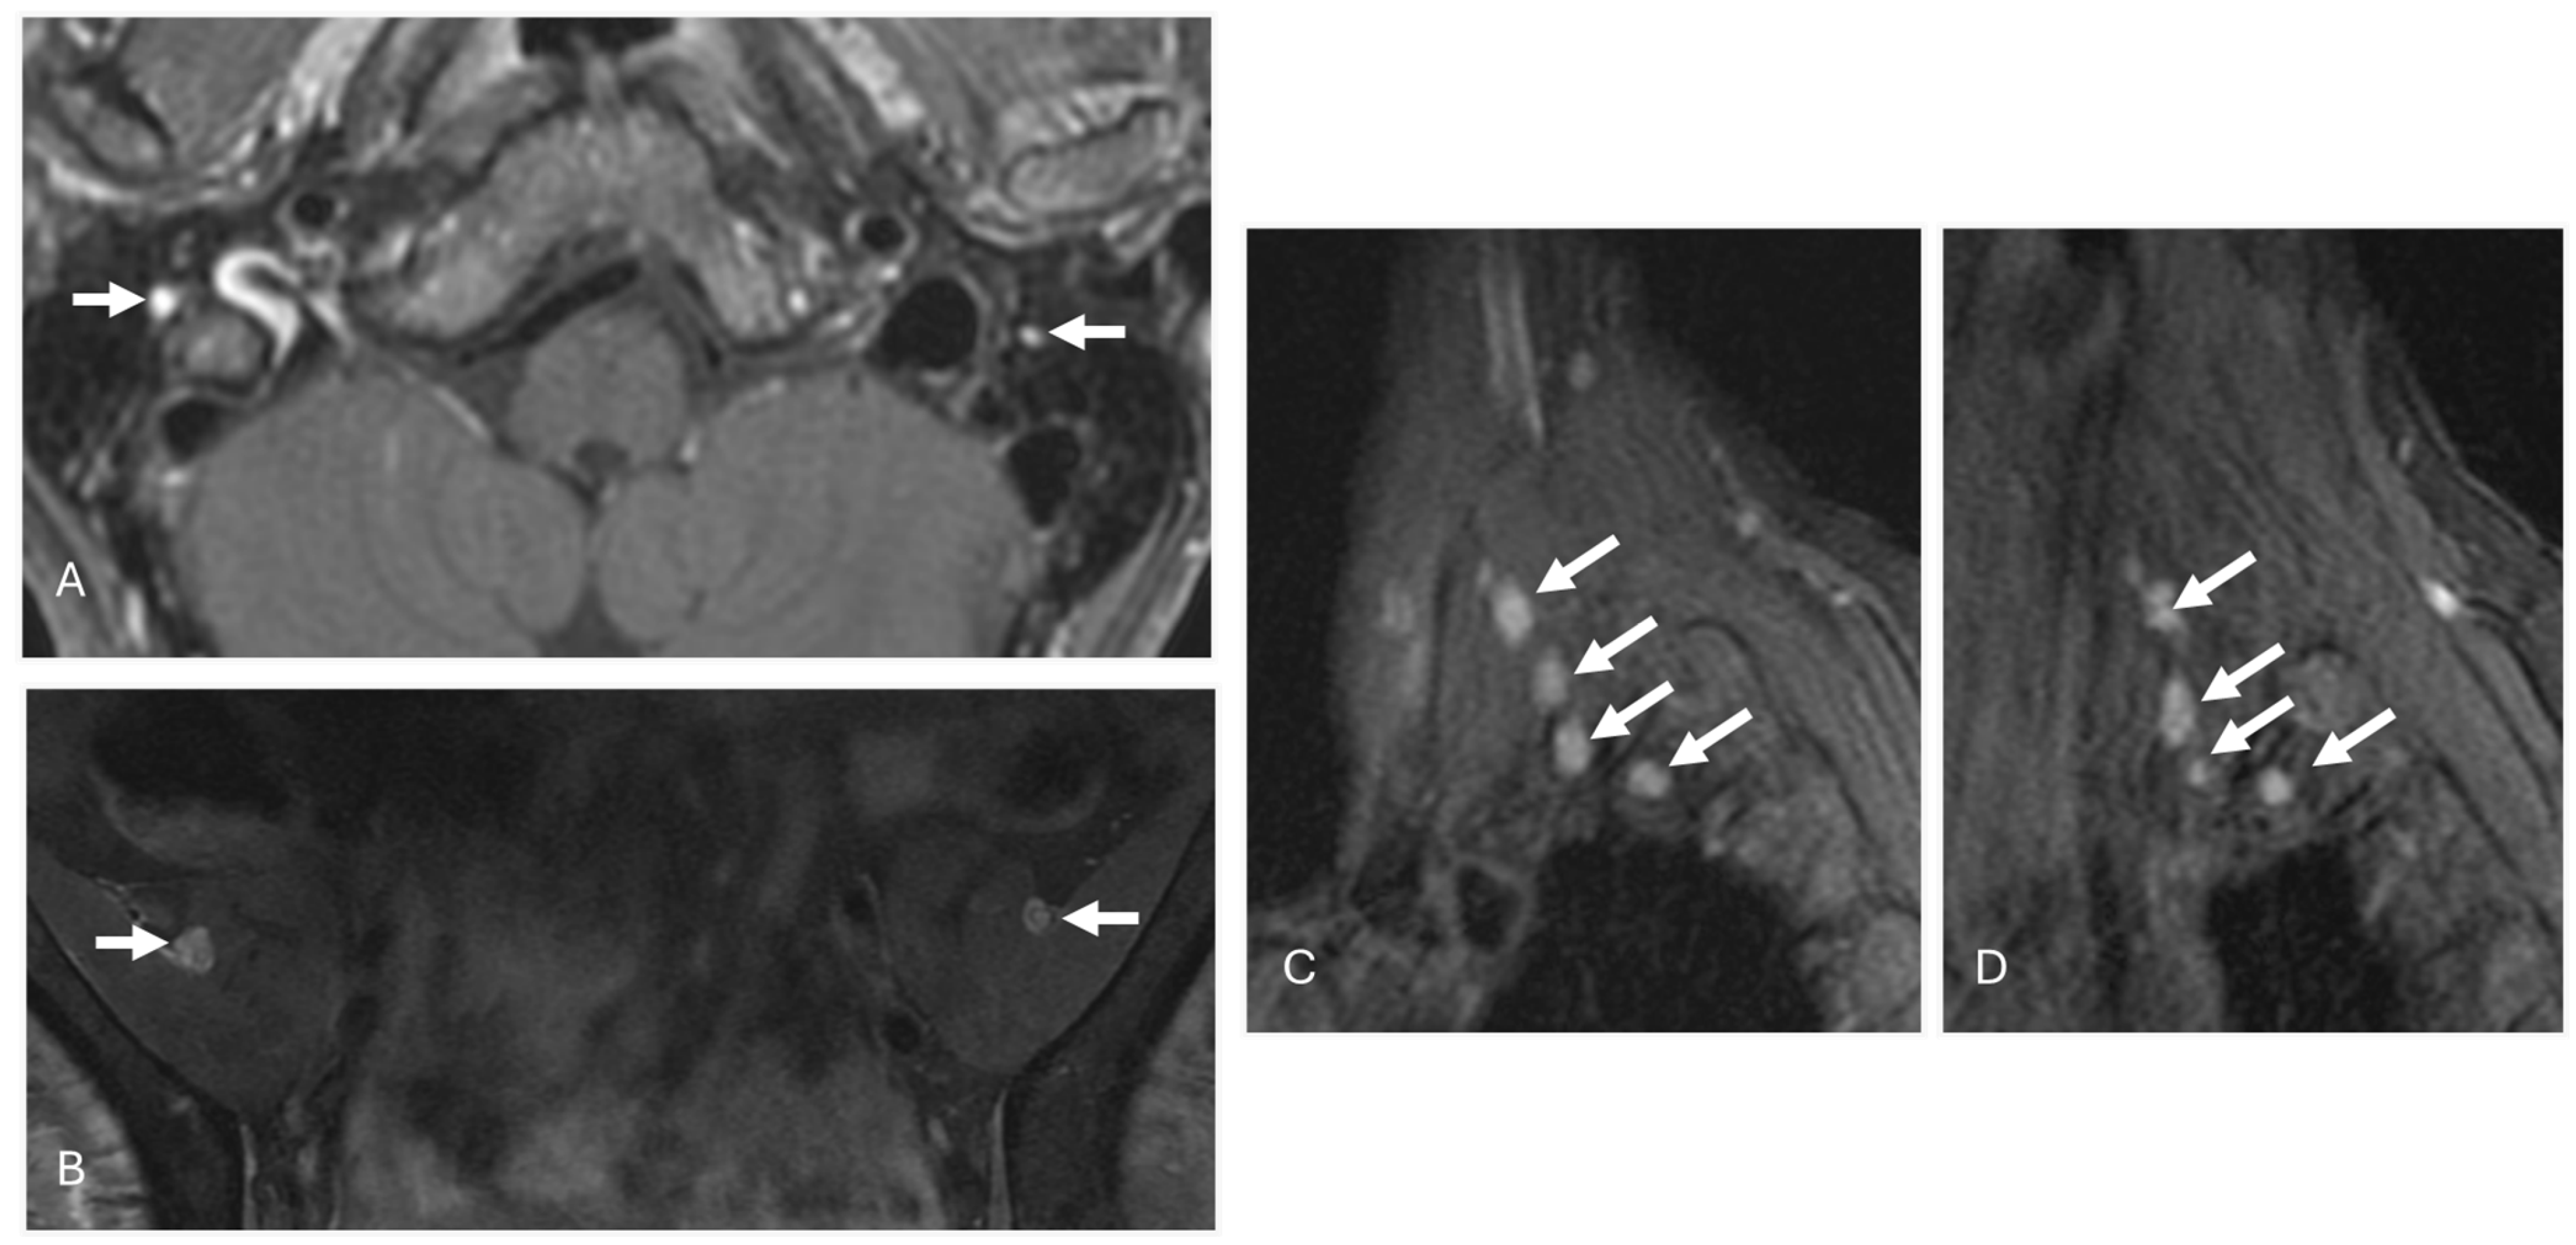

4. Monoclonal Gammopathy of Renal Significance (MGRS)